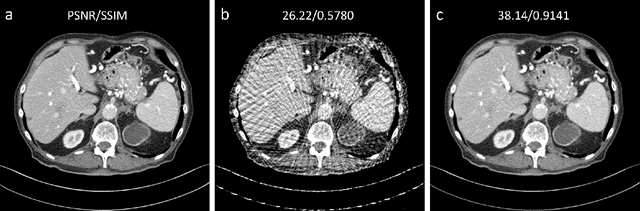

Sparse-view computed tomography (CT) can be used to reduce radiation dose greatly but is suffers from severe image artifacts. Recently, the deep learning based method for sparse-view CT reconstruction has attracted a major attention. However, neural networks often have a limited ability to remove the artifacts when they only work in the image domain. Deep learning-based sinogram processing can achieve a better anti-artifact performance, but it inevitably requires feature maps of the whole image in a video memory, which makes handling large-scale or three-dimensional (3D) images rather challenging. In this paper, we propose a patch-based denoising diffusion probabilistic model (DDPM) for sparse-view CT reconstruction. A DDPM network based on patches extracted from fully sampled projection data is trained and then used to inpaint down-sampled projection data. The network does not require paired full-sampled and down-sampled data, enabling unsupervised learning. Since the data processing is patch-based, the deep learning workflow can be distributed in parallel, overcoming the memory problem of large-scale data. Our experiments show that the proposed method can effectively suppress few-view artifacts while faithfully preserving textural details.